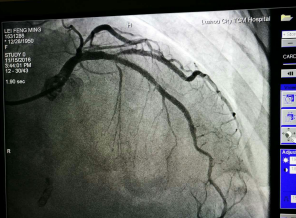

我院成功开展市属医院首例冠状动脉内膜旋磨术 在心脏血管内开“隧道”,用高速旋转的钻石磨头将堵塞心脏血管的钙化斑块磨碎,以此打通血管进行冠心病的介入治疗,这看起来像科幻电影里的场面,在我院实现。近日,我院完成了全市市属医院首例冠状动脉内膜旋磨手术,成功开通了血管,解除了患者长期存在的胸闷...